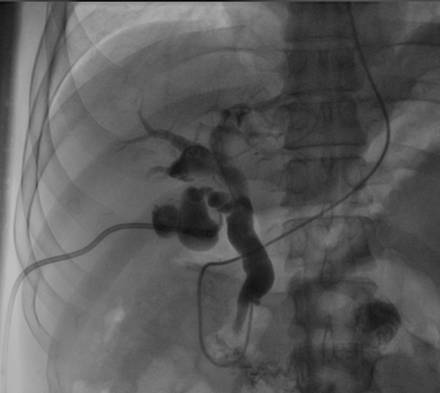

内镜逆行插管仅进入胰管,胆总管下段闭塞,插管不成功;内镜下放置胰管支架。 | |

经皮经肝胆道穿刺顺行疏通胆总管 |

胆管支架放置成功,造影剂顺利经支架流入肠道 |